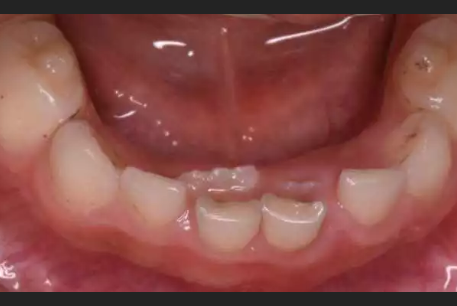

可如今,越来越多的小朋友出现换牙“程序”有点错乱的问题,还没等乳牙“下岗”恒牙就迫不及待“上岗”,于是,两颗牙并排在岗,只能请牙医通过“暴力”的方式强制要求乳牙“下岗”,否则将严重影响牙齿的美观与健康。

“双排牙的问题现在在临床上很常见,我们碰到每10个小朋友至少有5个存在,有些好一点的乳牙已经松动,而有些厉害的乳牙纹丝不动,只能通过外力拔除。”钱晓云医生说,之所以会有越来越多的小朋友出现双排牙,其实关键问题就出在家长的喂养方式上,太精细。

“牙齿就跟肌肉一样用进废退,尤其是小朋友在生长发育阶段,更需要多锻炼。”钱医生说,恒前牙一般都比乳前牙大1/3左右,如果不通过锻炼来促进颌骨的正常发育,恒牙就会因没有足够的空间长而排列不整齐,甚至是出现双排牙。这也就是为什么大家说“小时候牙齿太整齐换牙以后往往不太好看”。